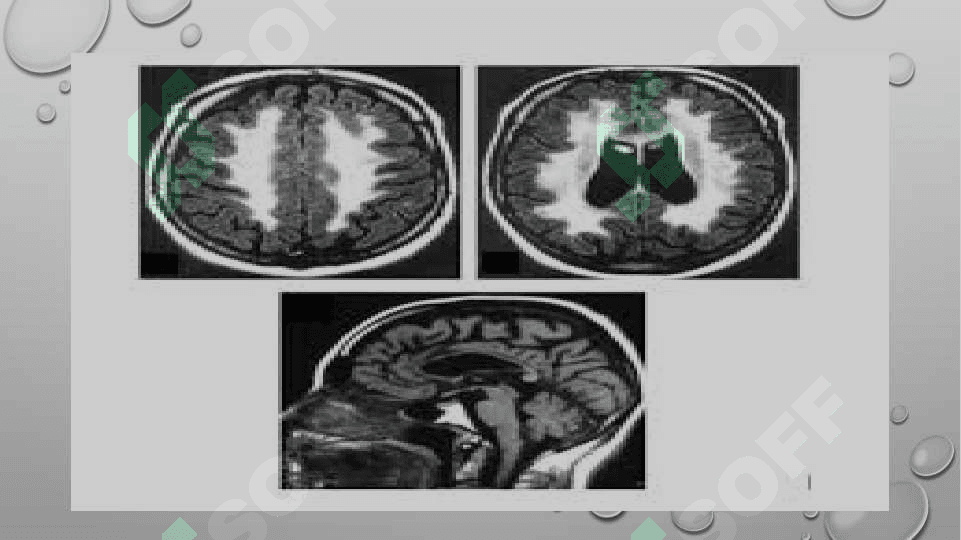

Metoxromatik leukodistrofiya